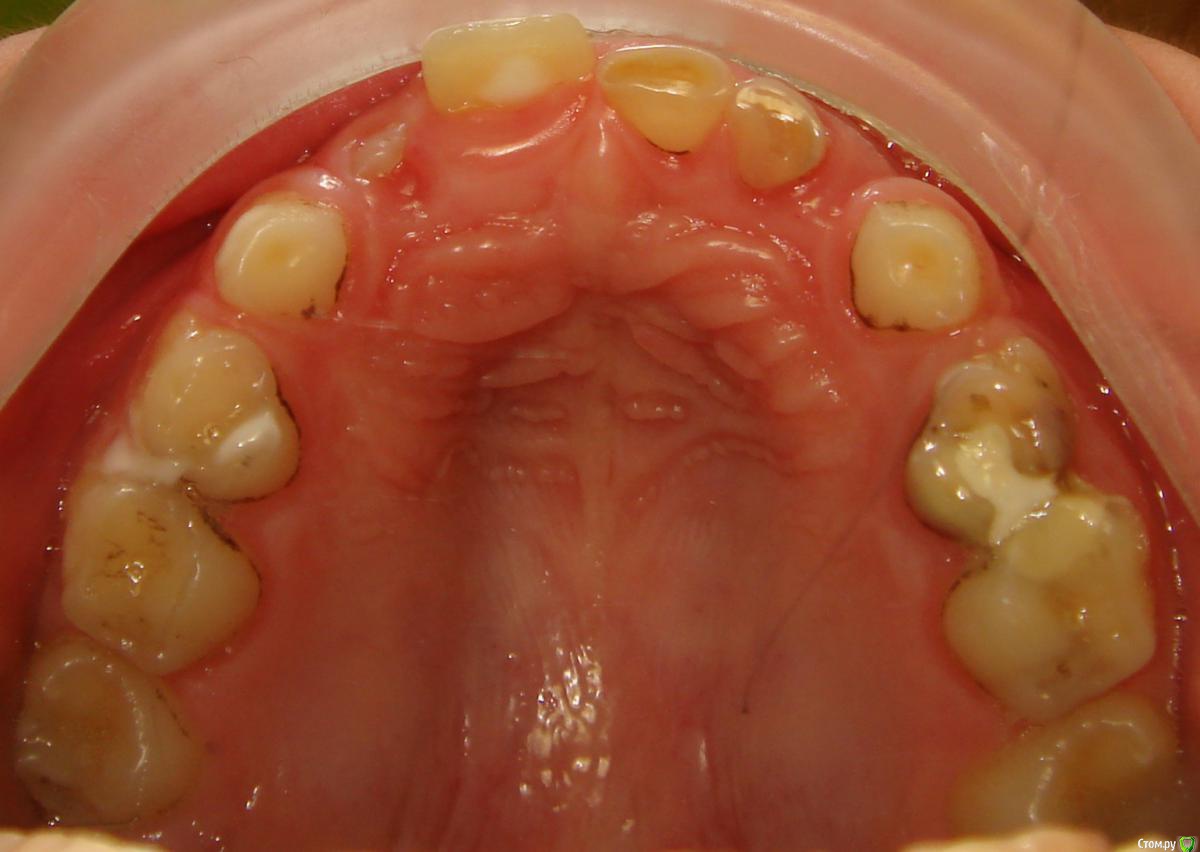

Opdihatop Опубликовано 9 января, 2017 Поделиться Опубликовано 9 января, 2017 Здравствуйте, коллеги! Хотел бы узнать ваше мнение по пациентке. Девочке 7 лет. План лечения в общем мне ясен и понятен. Меня интересует вопрос, когда лучше в данном случае убирать сверхкомплектный премоляр в области 21 зуба, потому что он начал двигать ц.л. вправо. Заранее спасибо! Ссылка на комментарий

Dok22 Опубликовано 11 января, 2017 Поделиться Опубликовано 11 января, 2017 Это не премоляр просто так виден 2-х мерный срез нужно КТ его грамотная интерпретация и хороший хирург.Сверхкомплектный удалять надо он блокирует 21 и 22. Ссылка на комментарий

Yana guapa Опубликовано 13 января, 2017 Поделиться Опубликовано 13 января, 2017 убрать молочный ц. резец. подождать 6-8 месяцев хотя бы (лучше год) - все ростковые зоны уже значительно выше будут, хирург не задет уже.сделать КТ. и удалить сверхкомплектный. Дать возможность опуститься ц. резцу.сильно долго ждать (до полного формирования корней) не вижу смысла. Очень похожа ситуация была у моей девочки (такое же расположение). - очень долго не хотел ц. резец спускаться. Райц-терапия в помощь)) вышел)) Ссылка на комментарий

Yana guapa Опубликовано 16 января, 2017 Поделиться Опубликовано 16 января, 2017 21? 61 . и 62 можно, у него все равно корень рассосался уже )) Ссылка на комментарий